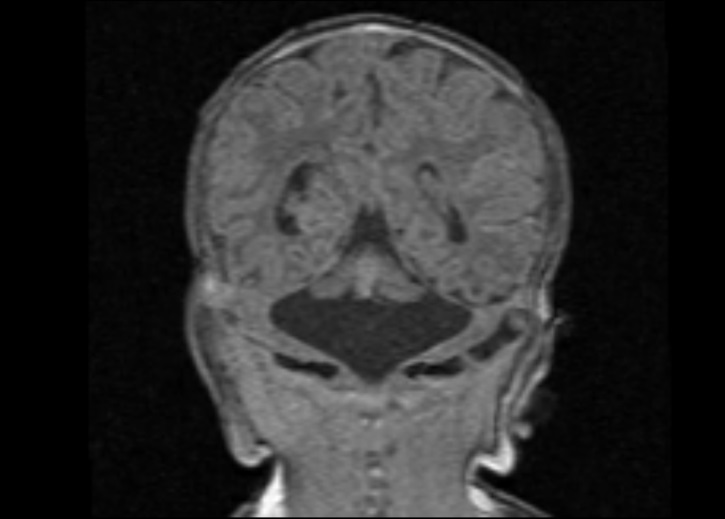

Figure 3 Coronal (a) and midsagittal (b) T1 MP-RAGE images of a female neonate on day 9 of life demonstrating severe hypoplasia of the brainstem and cerebellum with a “dragonfly-like shape” in (a).

This female patient was born at 41 1/7 weeks of gestation after an uneventful pregnancy. She was the second child of healthy non-consanguineous German parents. Her birth weight was 3,805 g (69th centile), head circumference 34.7 cm (34th centile) and her Apgar scores were 7 and 9 at 1 and 5 minutes, respectively. Due to muscular hypertonia with general hyperexcitability and limb tremors, the baby was admitted to the NICU. She had seizure-like episodes beginning on day 6, with high muscle tone, eye deviation, bilateral limb cloni and cyanosis. The baby was treated for suspected epileptic seizures with intravenous pyridoxine and phenobarbital. Neuropediatric examination revealed initial marked muscular hypertonia with flexion posture of the arms and legs, reduced spontaneous movements and an exaggerated startle response to touch and noise, with clonus-like oscillations of the limbs. Routine laboratory examinations, including metabolic workup, EEG and amplitude integrated EEG were normal. Cranial ultrasound revealed pronounced cerebellar hypoplasia and cerebral MRI confirmed severe hypoplasia of the cerebellum and brainstem (Figure 3). As the clinical course progressed, the hypertonia of the limbs improved and the seizure-like hypertonic attacks disappeared without medical treatment. By the end of her second week of life, the baby became floppy with muscular hypotonia of the trunk and feeding by a nasogastric tube was necessary due to weak suckling. Targeted genetic panel sequencing for the more common genetic forms of pontocerebellar hypoplasia was initiated on day 13. The following genes were included in the panel: B3GALNT1, CASK, DCX, EXOSC3, RARS2, RELN, SEPSECS, TSEN2, TSEN34, TSEN54, VRK1. The clinical diagnosis of a pontocerebellar hypoplasia (PCH) was confirmed by the presence of the homozygous hotspot mutation p.Ala307Ser (class 5: pathogenic variant [15]) in the TSEN54 gene on day 28 of life [16,17]. The child was discharged from the hospital in a stable condition with continued nasogastric feeding at the age of 4 weeks.